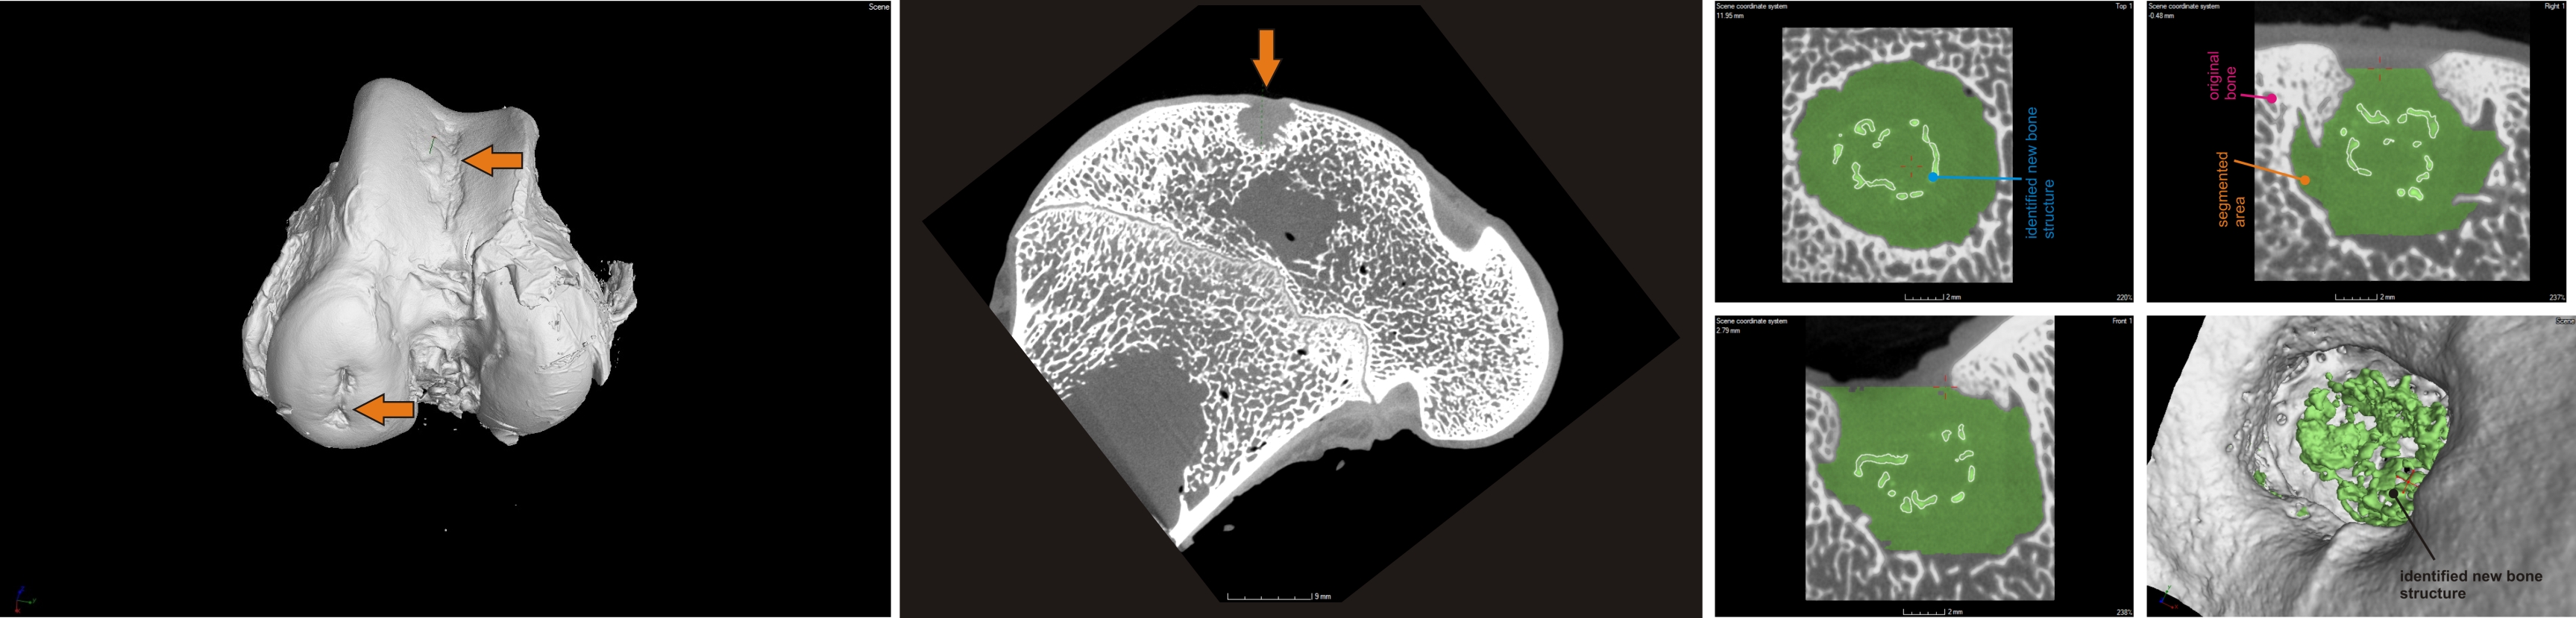

Industrial computed tomography enables non-destructive non-contact measurement and scanning of parts in their entire volume using X-ray radiation. By using computed tomography (CT), we obtain a comprehensive view of the part from any angle and in any section. Volumetric data or a cloud of points representing the volume of the part is obtained from a number of radiographs (X-ray images) created when the part is scanned while it is rotating around a vertical axis. The laboratory is focused on the processing and visualization of volume data, evaluation of dimensions and shape deviations of scanned objects, analysis of defects in materials and other analyses.